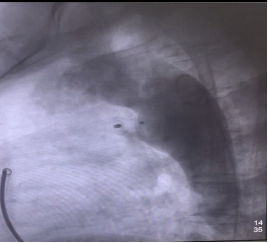

术前心脏彩超 术后心脏彩超

术后,患者胸闷症状明显好转,第二天便能下地活动。复查心脏彩超显示患者主动脉-肺动脉异常分流消失,封堵器固定良好。